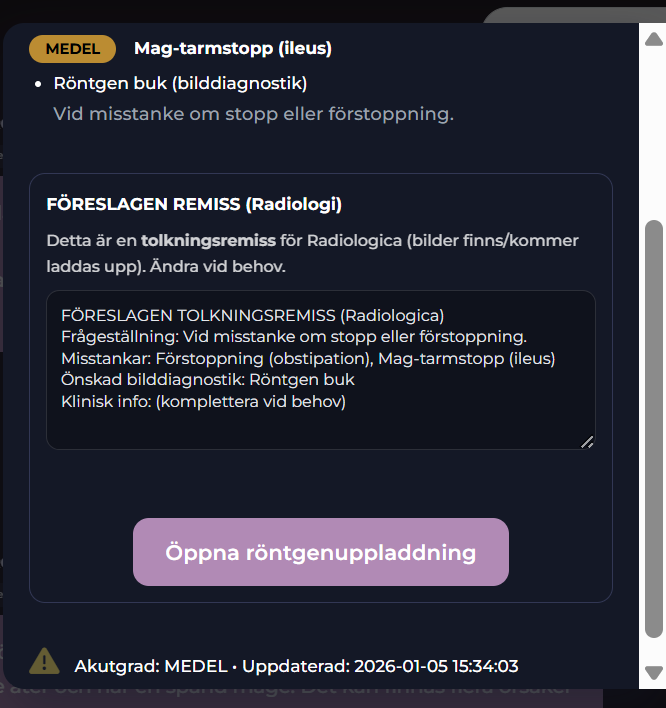

Ladda upp röntgenbilder.

Radiologica tar emot uppladdade röntgenbilder samt remissens frågeställning och gör en analys. Du laddar upp röntgenbilden och klickar på Tolka bilder.